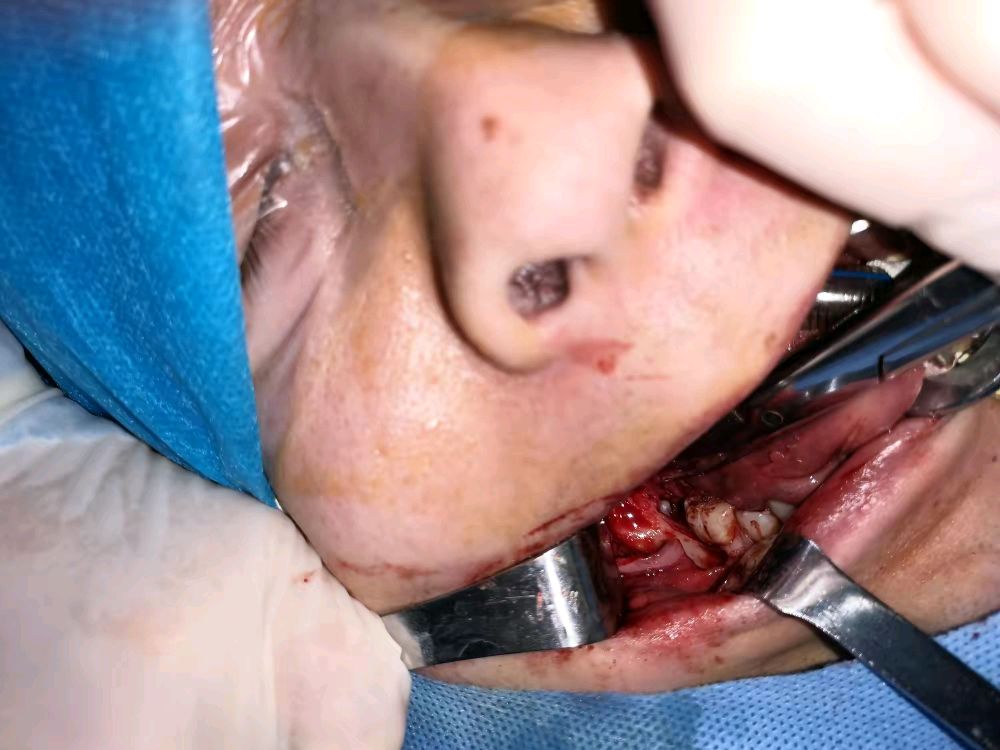

先来一张整图吧,一个170斤但并不显脸大的某男,连第二磨牙都没有空间萌出,不显脸大原来实在是颌骨太窄小了,张嘴的状态我能感受到那一大坨颊脂垫那么纯正的脂肪正在拼命往嘴里寻找空间,无以言表的无力感与苦水啊…

看见这一坨肉了吧,有时候智齿倒着不怕,怕的是这一大坨肉死活拉不开,那才是看不见,“磨”不着(拔牙都需要告诉手机磨开分牙)。